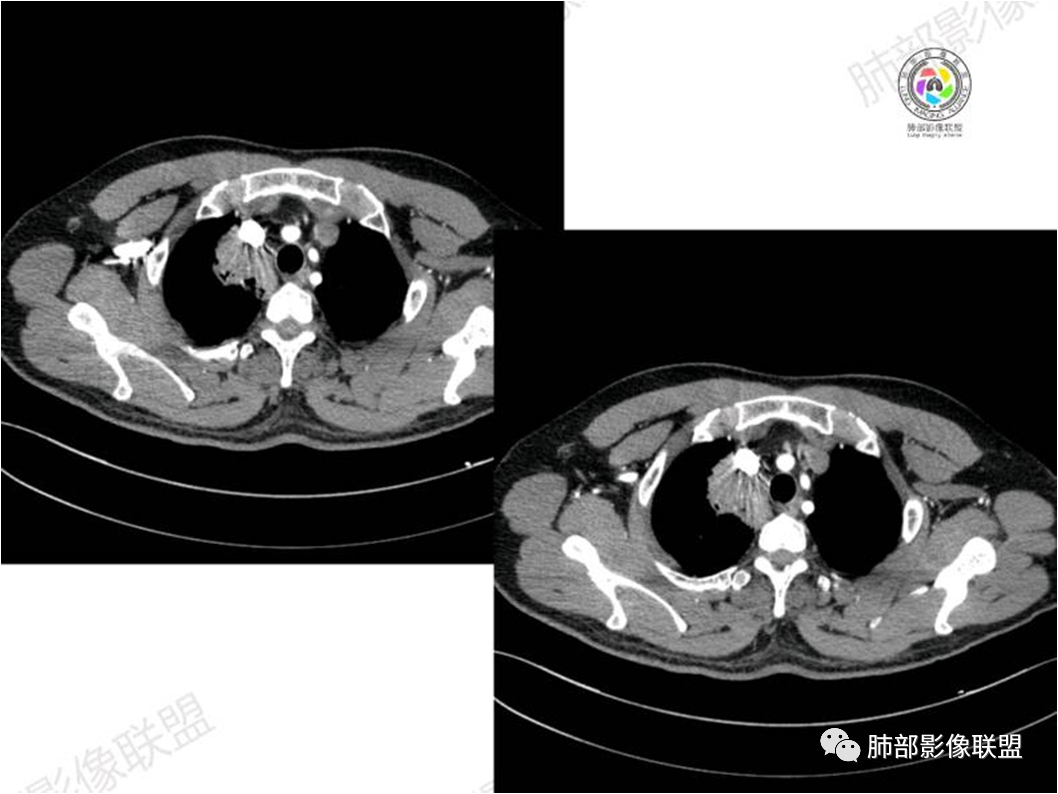

胸部CT:

中年男性,偶有咳嗽,右肺上叶近纵膈旁占位,内可见僵硬的支气管和小空泡征,病灶边缘可见分叶,毛刺,增强病灶中度以上不均匀强化,可见血管造影征,考虑恶性病变,腺癌可能性大。

右肺上叶纵隔胸膜侧一实性肿块,与纵隔胸膜宽基底相连,局部脂肪间隙消失,形态欠规则,内部可见多个小空泡,平扫密度尚均匀,增强后可见点条状强化,内部穿行血管,周围肺组织干净,纵隔淋巴结略肿大,男性44岁,只有咳嗽,考虑恶性肿瘤,腺癌,鳞癌。鉴别结核,OP,炎性假瘤。

右肺上叶近纵膈旁肿块,密度均匀,边缘分叶,毛刺,气管受压变窄,不均匀强化,可见血管造影征,考虑淋巴瘤,鉴别炎性假瘤。

中年男性,右肺上叶纵隔旁软组织肿块,边缘膨隆、毛糙,可见多发分叶,支气管穿行,部分截断,增强后密度欠均匀,纵隔内见多发小淋巴结,首先考虑恶性,腺癌,鉴别淋巴瘤

中年男性,右肺上叶纵隔旁肿瘤,稍膨隆,有毛刺,支气管穿行,远端闭塞,强化均匀,血管走行尚可,考虑淋巴瘤可能性大(支气管远端闭塞,不太符合),鉴别腺癌(气管穿行后闭塞,不太符合),op(病灶稍膨隆)

患者中年男性,咳嗽就诊,无其他不适。胸部CT:右肺上叶尖段上纵膈旁肿块,边界清楚,边缘光滑,内见支气管受压变窄,伴阻塞性改变,增强均匀强化,见血管造影征。综合考虑恶性病变,小细胞肺癌或淋巴瘤。气管镜活检应能明确。

中年男性,右肺上叶纵隔旁实性病灶,边缘有彭隆,有平直,有分叶,有尖角,病灶边缘中心可见支气管征,周围少许磨玻璃,边缘模糊,增强后动脉期病灶可见强化血管影,渐进性强化,临近血管界限清晰。考虑炎性病灶,普通炎性肉芽肿?结核?炎性肌纤维母细胞瘤?鉴别腺癌,淋巴瘤

病灶紧贴纵隔胸膜

糊墙,胸膜外未见明显侵犯迹象

病灶整体狭长一些

边缘平直、凹陷为主

支气管外侧带的通畅,片内侧带的似乎中近端狭窄,堵塞

内部肺动脉走形还可以

近端支气管壁弥漫增厚

强化均匀

整体炎性的特点比较明显